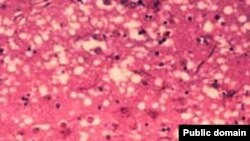

Поражение ткани мозга прионами с образованием характерной губчатой структуры, которое приводит к «коровьему бешенству»

Суд оправдал врачей, которым инкриминировалось массовое заражение болезнью Кройтцфельдта-Якоба («коровьим бешенством»), жертвами которого стали 117 детей. В 1980-е годы прошлого века пострадавшие получали инъекции гормона роста, который в извлекался из трупного материала. Большинству обвиняемых больше 80 лет. Cуд счел недостаточно убедительными аргументы обвинения.